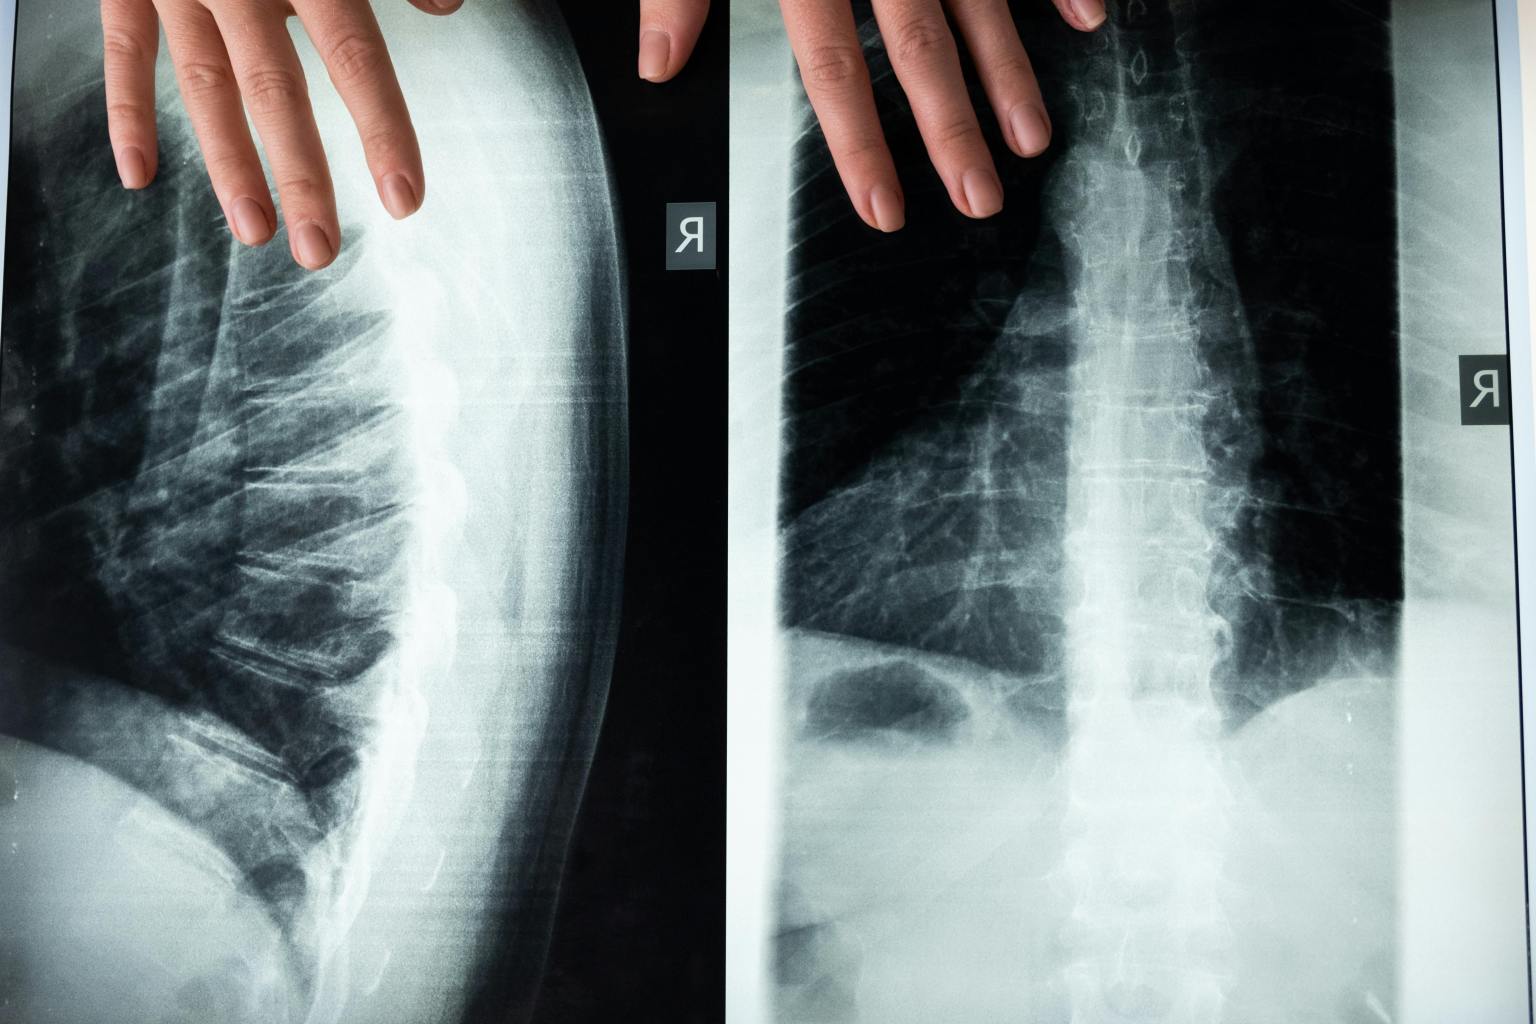

Different Imaging Procedures

Each imaging procedure carries a distinct level of risk based on the type of X-ray being used and the specific area being examined. For instance, CT scans and interventional procedures are associated with higher doses of radiation compared to standard X-rays. In fact, the radiation exposure from these procedures can range from 100 to 1000 times higher than that of a typical chest X-ray.

Medical practitioners will carefully consider the necessity of these higher-dose procedures against the potential health risks when determining the most appropriate imaging method for a particular issue. It’s essential for patients to be informed about the level of radiation exposure associated with each imaging procedure and to discuss any concerns with their healthcare provider.